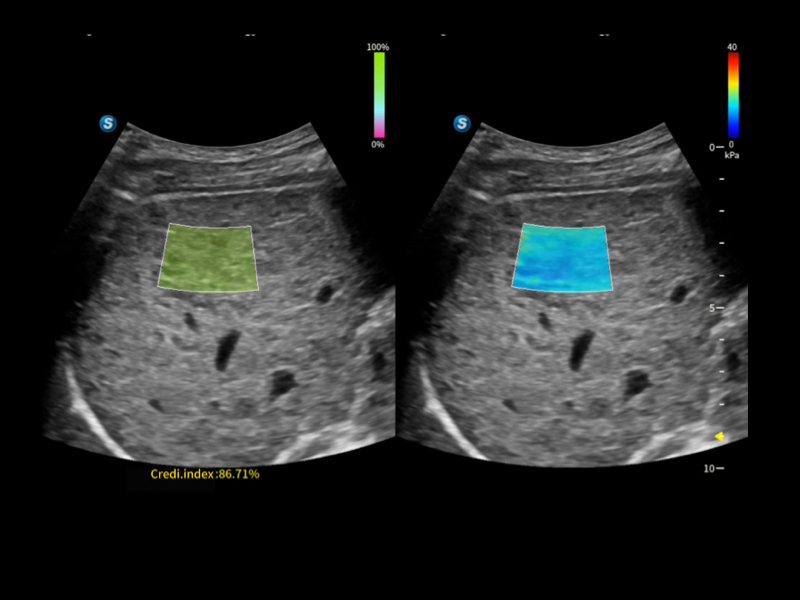

作為開立醫(yī)療全新打造的超高端旗艦超聲產(chǎn)品,從探頭抬起喚醒開啟掃查到多維探頭發(fā)射接收,通過先進(jìn)的場(chǎng)成像發(fā)射、自適應(yīng)聚合重建等技術(shù),基于RF Data原始射頻數(shù)據(jù)在圖像生成、高端功能等方面實(shí)現(xiàn)突破,提供多科室綜合臨床解決方案。

自適應(yīng)聚合重建技術(shù)